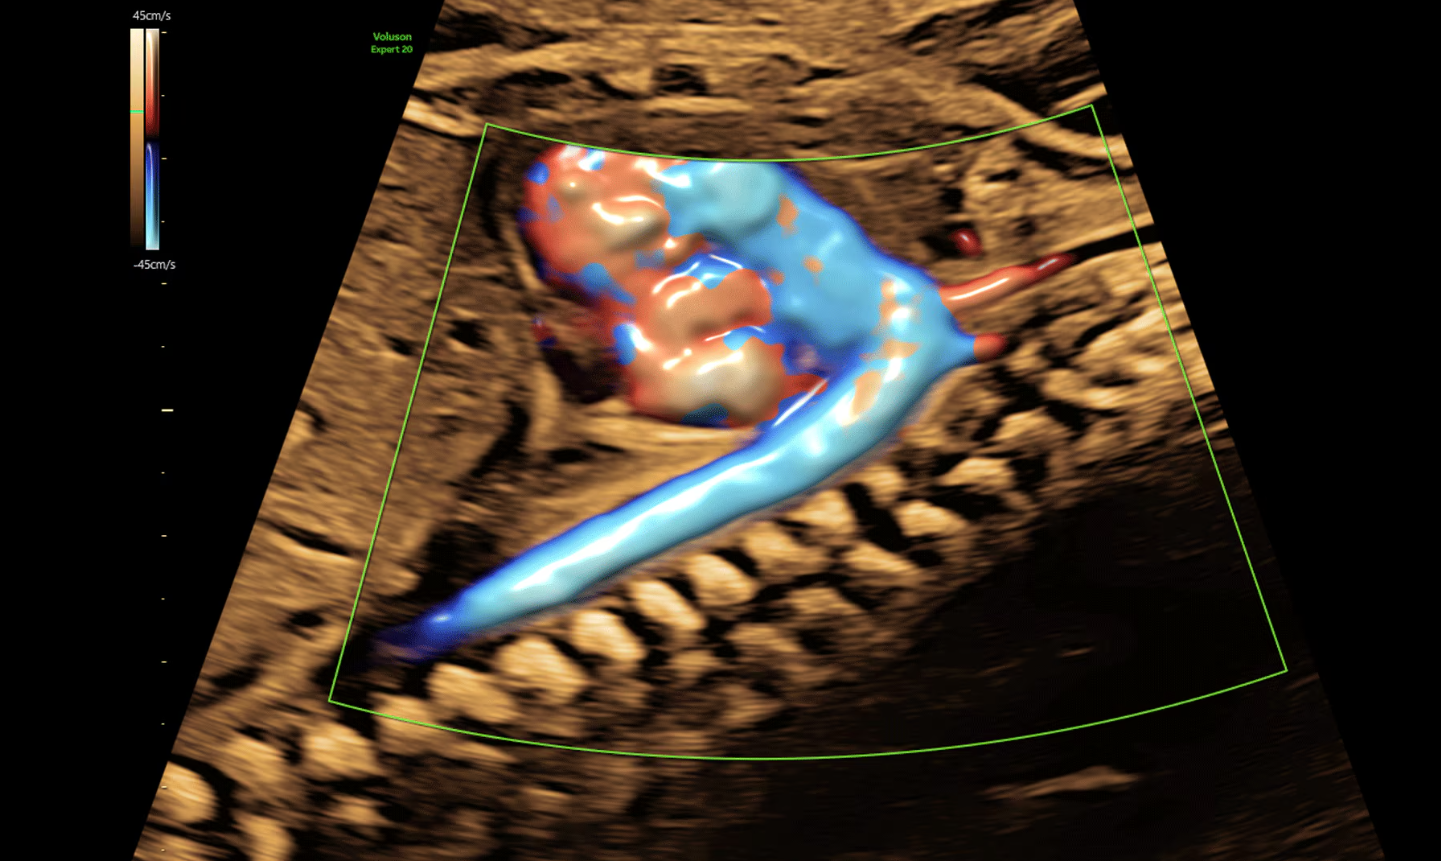

- Effettuare esami di diagnostica prenatale con tecnologia 3D/4D.